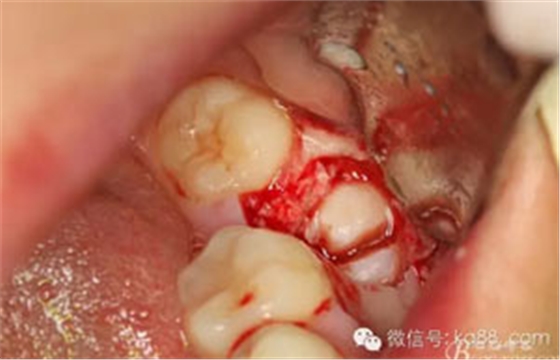

圖13.縱分牙冠

圖14.分開近遠(yuǎn)中牙冠及牙根及周圍囊壁。